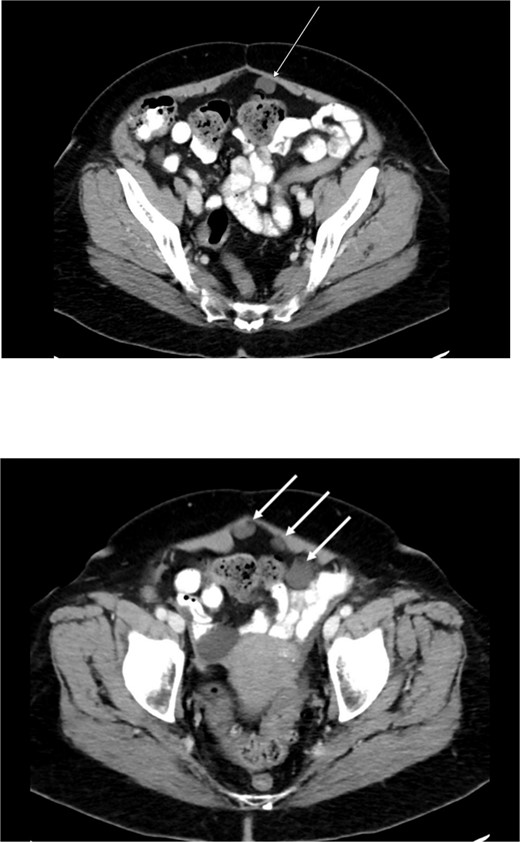

Preoperative abdominal computed tomography revealed a mass in the ascending colon (Fig. 1) and multiple nonspecific cystic lesions in the peritoneal cavity involving the abdomen and pelvis (Fig. 2). Normally, carcinomatosis would be suspected in a patient with mucinous adenocarcinoma of the colon. However, the radiographic findings were not definitive for carcinomatosis, and the history of abdominal ‘cysts’ 20 years previously further confused the situation. The differential at the time included malignant carcinomatosis, benign endometriotic cysts, and cystic peritoneal reaction to previously placed intraperitoneal hernia mesh. Carcinoembryonic antigen measured 0.8 ng/mL.

Computed tomography abdomen/pelvis—arrows indicate peritoneal cysts.